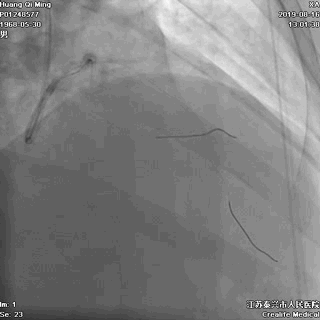

术后即刻效果满意

CCTA的指导价值

药物洗脱球囊最核心的操作要领:一是充分的斑块预处理,二是药物球囊迅速到达目标病变位置,从而实现最有效的药物定点释放。其中,CCTA的评估功能不容小觑。结合上面的病例,术前CCTA检查的必要性如下:

1、明确了LAD病变位于血管的中远段,比较弥漫,病变段血管整体偏细,是应用药物球囊的适应症;

一句话,CCTA提示LAD中远段的小血管病变,可以使用药物洗脱球囊处理(给术者吃了颗定心丸)。